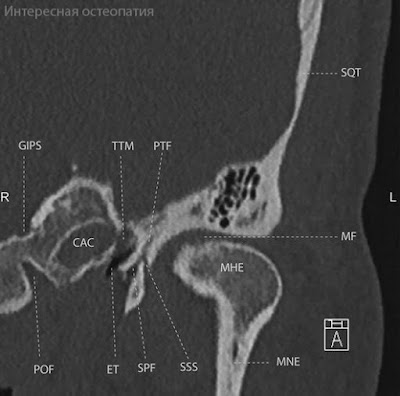

Височно-нижнечелюстной сустав (articulation temporomandibularis) образован головкой нижней челюсти и нижнечелюстной ямкой височной кости (рис. 1). Его суставные поверхности покрыты волокнистым хрящом.

Рис. 1. Височно-нижнечелюстной сустав:

а — вид с латеральной стороны: 1 — латеральная связка; 2 — суставной бугорок; 3 — скуловая дуга; 4 — шилонижнечелюстная связка; 5 — шиловидный отросток;

б — вид с медиальной стороны: 1 — клиновидно-нижнечелюстная связка; 2 — медиальная связка; 3 — шиловидный отросток; 4 — шилонижнечелюстная связка; 5 — крыловидно-нижнечелюстная связка, 6 — медиальная пластинка крыловидного отростка;

в — сагиттальный распил сустава: 1 — капсула сустава; 2 — суставной хрящ; 3 — верхняя суставная щель; 4 — суставной диск; 5 — верхняя синовиальная мембрана; 7 — нижняя синовиальная мембрана; 8 — нижняя суставная щель; 9 — головка нижней челюсти; 10— шилонижнечелюстная связка; 11— шиловидный отросток;

г — положение нижней челюсти при опускании нижней челюсти: 1 — головка нижней челюсти в исходном положении; 2 — головка нижней челюсти при открывании рта; 3 — латеральная крыловидная мышца при открывании рта; 4 — та же мышца в исходном положении; 5 — язычок нижней челюсти — неподвижная точка при открывании рта; 6 — двубрюшная мышца (переднее брюшко в исходном положении и при открывании рта); 7 — шилоподъязычная мышца; 8 — клиновидно-нижнечелюстная связка;

д — положение осей головок нижней челюсти